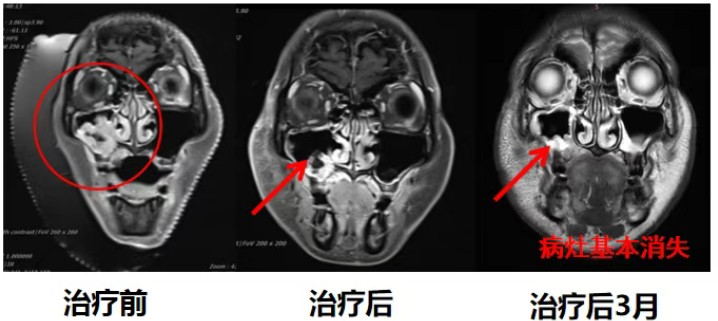

Another characteristic of adenoid cystic carcinoma (ACC) is its resistance to radiotherapy and chemotherapy, which easily leads to local recurrence and distant metastasis, making treatment difficult. As a precise tumor treatment method, heavy ions can accurately irradiate the tumor site with extremely high precision and strong penetration ability, ensuring that tumors of different depths and sizes are precisely enveloped within the Bragg peak region. Heavy ions exhibit a higher relative biological effectiveness (RBE) against ACC, which is not sensitive to conventional photon therapy, thereby enhancing the lethality to the tumor. In the radiotherapy of head and neck ACC, heavy ion radiotherapy can provide a more precise dose distribution, promoting high-dose irradiation of the tumor volume while protecting the surrounding normal tissues. In recent years, we have treated ACC patients in various head and neck regions, such as the base of the tongue, hard palate, lacrimal gland, maxillary sinus, etc., all achieving satisfactory results while protecting normal organs.

To date, head and neck adenoid cystic carcinoma has become the third major disease treated with carbon ion therapy in our department. Carbon ion radiotherapy is a treatment method with good efficacy and low toxic side effects, suitable for patients with unresectable, postoperative residual, radiotherapy-resistant, or recurrent head and neck adenoid cystic carcinoma. A prospective Phase III trial comparing conventional photon radiotherapy and heavy ion radiotherapy for ACC found that the 10-year local control (LC) rate for heavy ion therapy was 56%, compared to 17% for conventional photon radiotherapy. In a retrospective study, the 5-year LC rate in the heavy ion therapy group was significantly higher than 75%, whereas it was 32% in the photon therapy group. Compared to conventional photon therapy, heavy ion therapy significantly improved the local control rate and overall survival rate of ACC. A comprehensive review of the literature indicates that carbon ion therapy can be considered as one of the primary treatment methods for ACC.